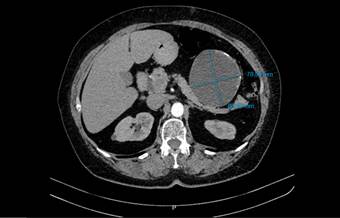

Se realizó una ecografía de abdomen total que informó una imagen quística de 8 x 7 cm, en íntimo contacto con la cola del páncreas. Posteriormente una tomografía computarizada de abdomen con contraste reportó una lesión hipodensa de aspecto quístico, de 86,6 x 78,5 mm, en contacto con la curvatura mayor del estómago, el cuerpo y la cola del páncreas, con paredes irregularmente engrosadas y calcificaciones periféricas aisladas en su interior. Como primera posibilidad se sugirió un tumor del estroma gastrointestinal (GIST, por sus siglas en inglés) (figuras 1 y 2). La endoscopia de vías digestivas altas diagnosticó una gastropatía antrocorporal no erosiva sin hallazgos patológicos adicionales.